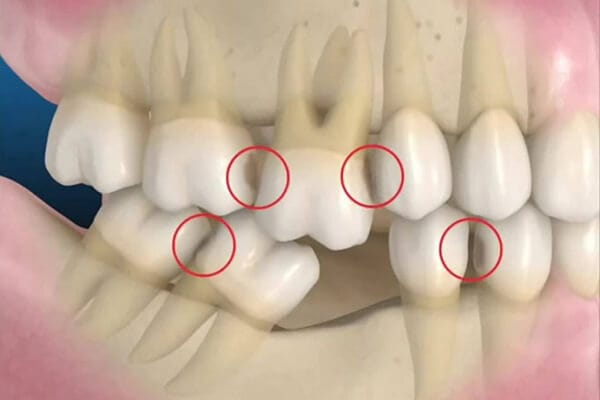

– Gây ra hiện tượng các răng trên cung hàm di chuyển. Khi trên cung hàm xuất hiện khoảng trống, các răng kế cận sẽ bị xô lệch, đổ nghiêng tràn sang khoảng trống mất răng. Và những chiếc răng đối diện ở hàm trên hoặc hàm dưới răng cấm cũng sẽ trồi lên làm mất cân bằng với các răng còn lại.